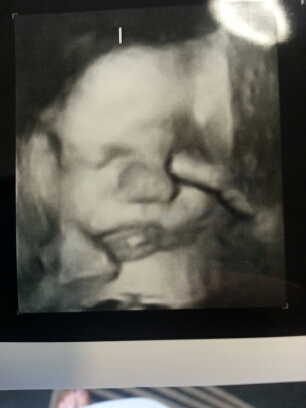

Look how perfect she is!!!